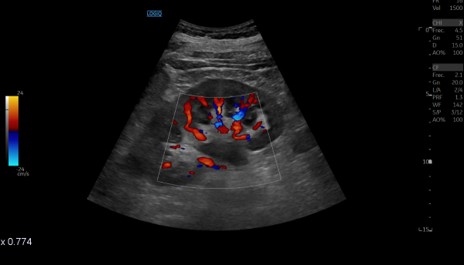

Ureterohidronefrosis grado I-II izquierda secundaria a litiasis en el uréter distal.

La ecografía se ha vuelto una herramienta clave en urgencias para valorar a los pacientes con posible cólico renal. Aunque no siempre permite ver todos los cálculos de forma directa, sí ofrece información muy útil: muestra si hay hidronefrosis, permite intuir si existe una obstrucción importante y ayuda a detectar situaciones que podrían complicar el cuadro, como una infección asociada. Su rapidez, disponibilidad y el hecho de no usar radiación la convierten en la primera prueba ideal.